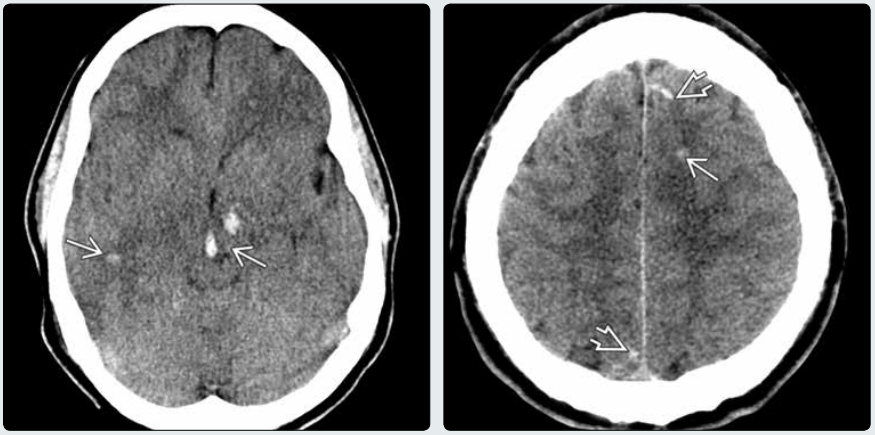

(左图)一位严重的非冲击性脑损伤患者的平扫 CT 显示弥散性脑水肿伴脑室缩小,脑沟裂及脑池变浅。弥散性轴索损伤(DAI)可见皮层下白质、中脑及左侧丘脑点线状的出血灶→

(右图)同一患者更多层面头侧扫描显示放射冠→与皮层下白质➪的其他出血性病灶